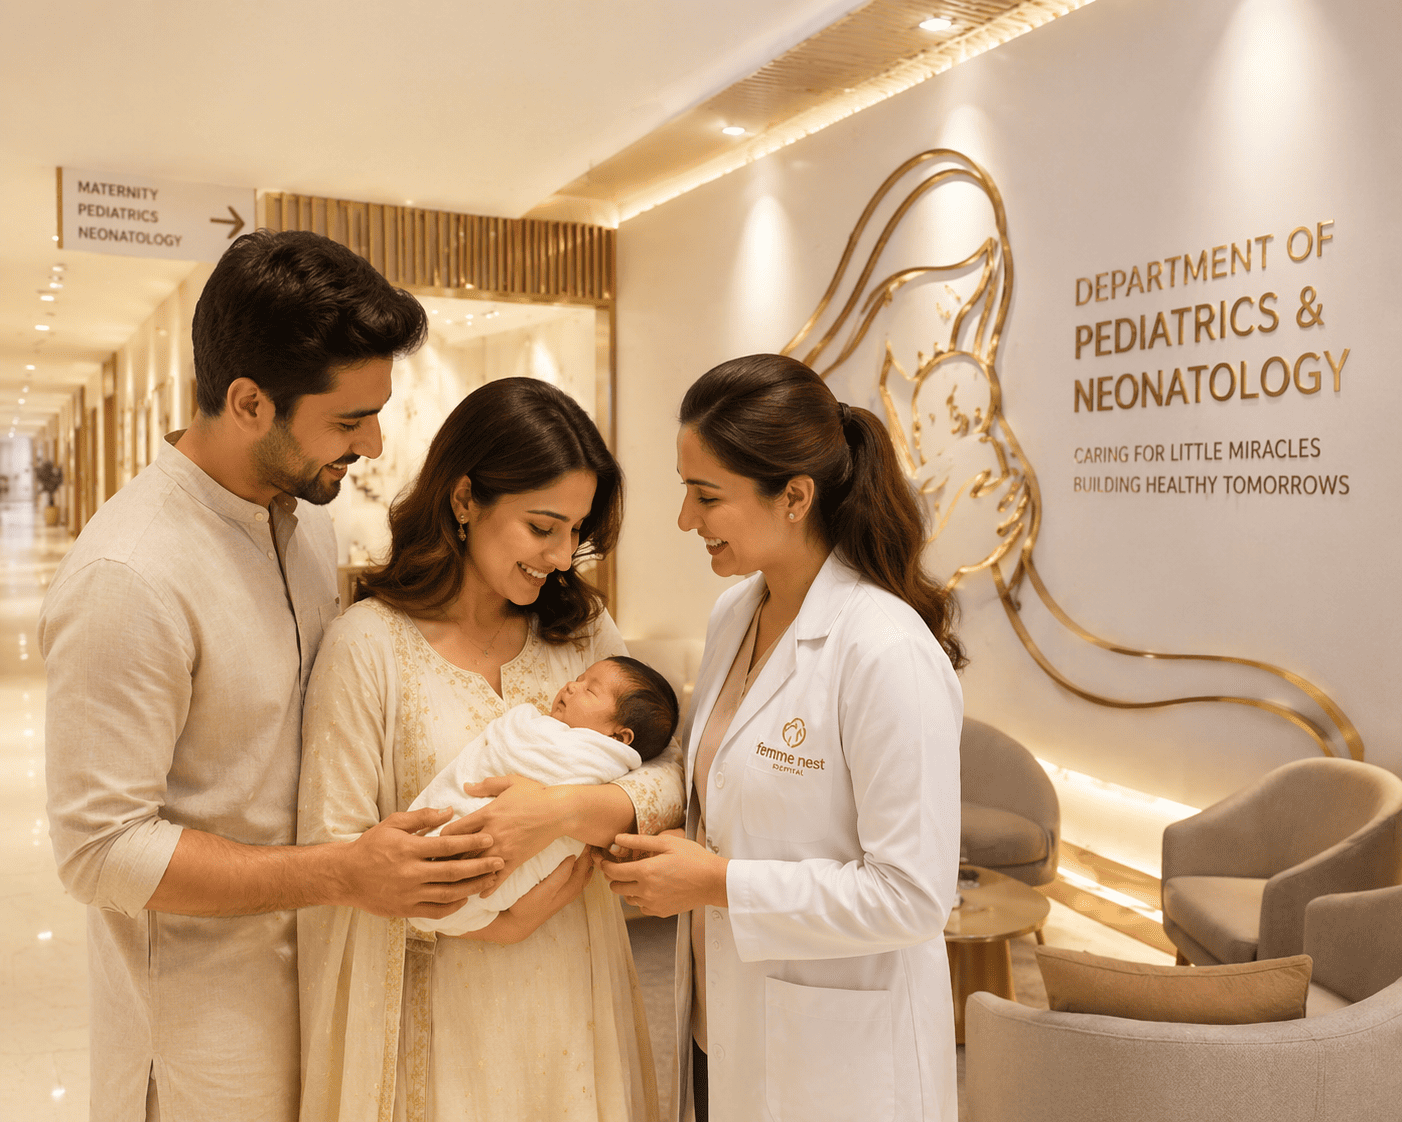

Neonatology & Pediatrics

Tiny lives deserve the biggest care — level-III NICU and 24×7 paediatric specialists.

Care That Begins at First Breath

Our neonatology programme follows globally recognised protocols for family-centred care. Parents are welcomed into the NICU, kangaroo-mother-care is actively encouraged, and breastfeeding support is offered throughout the stay.